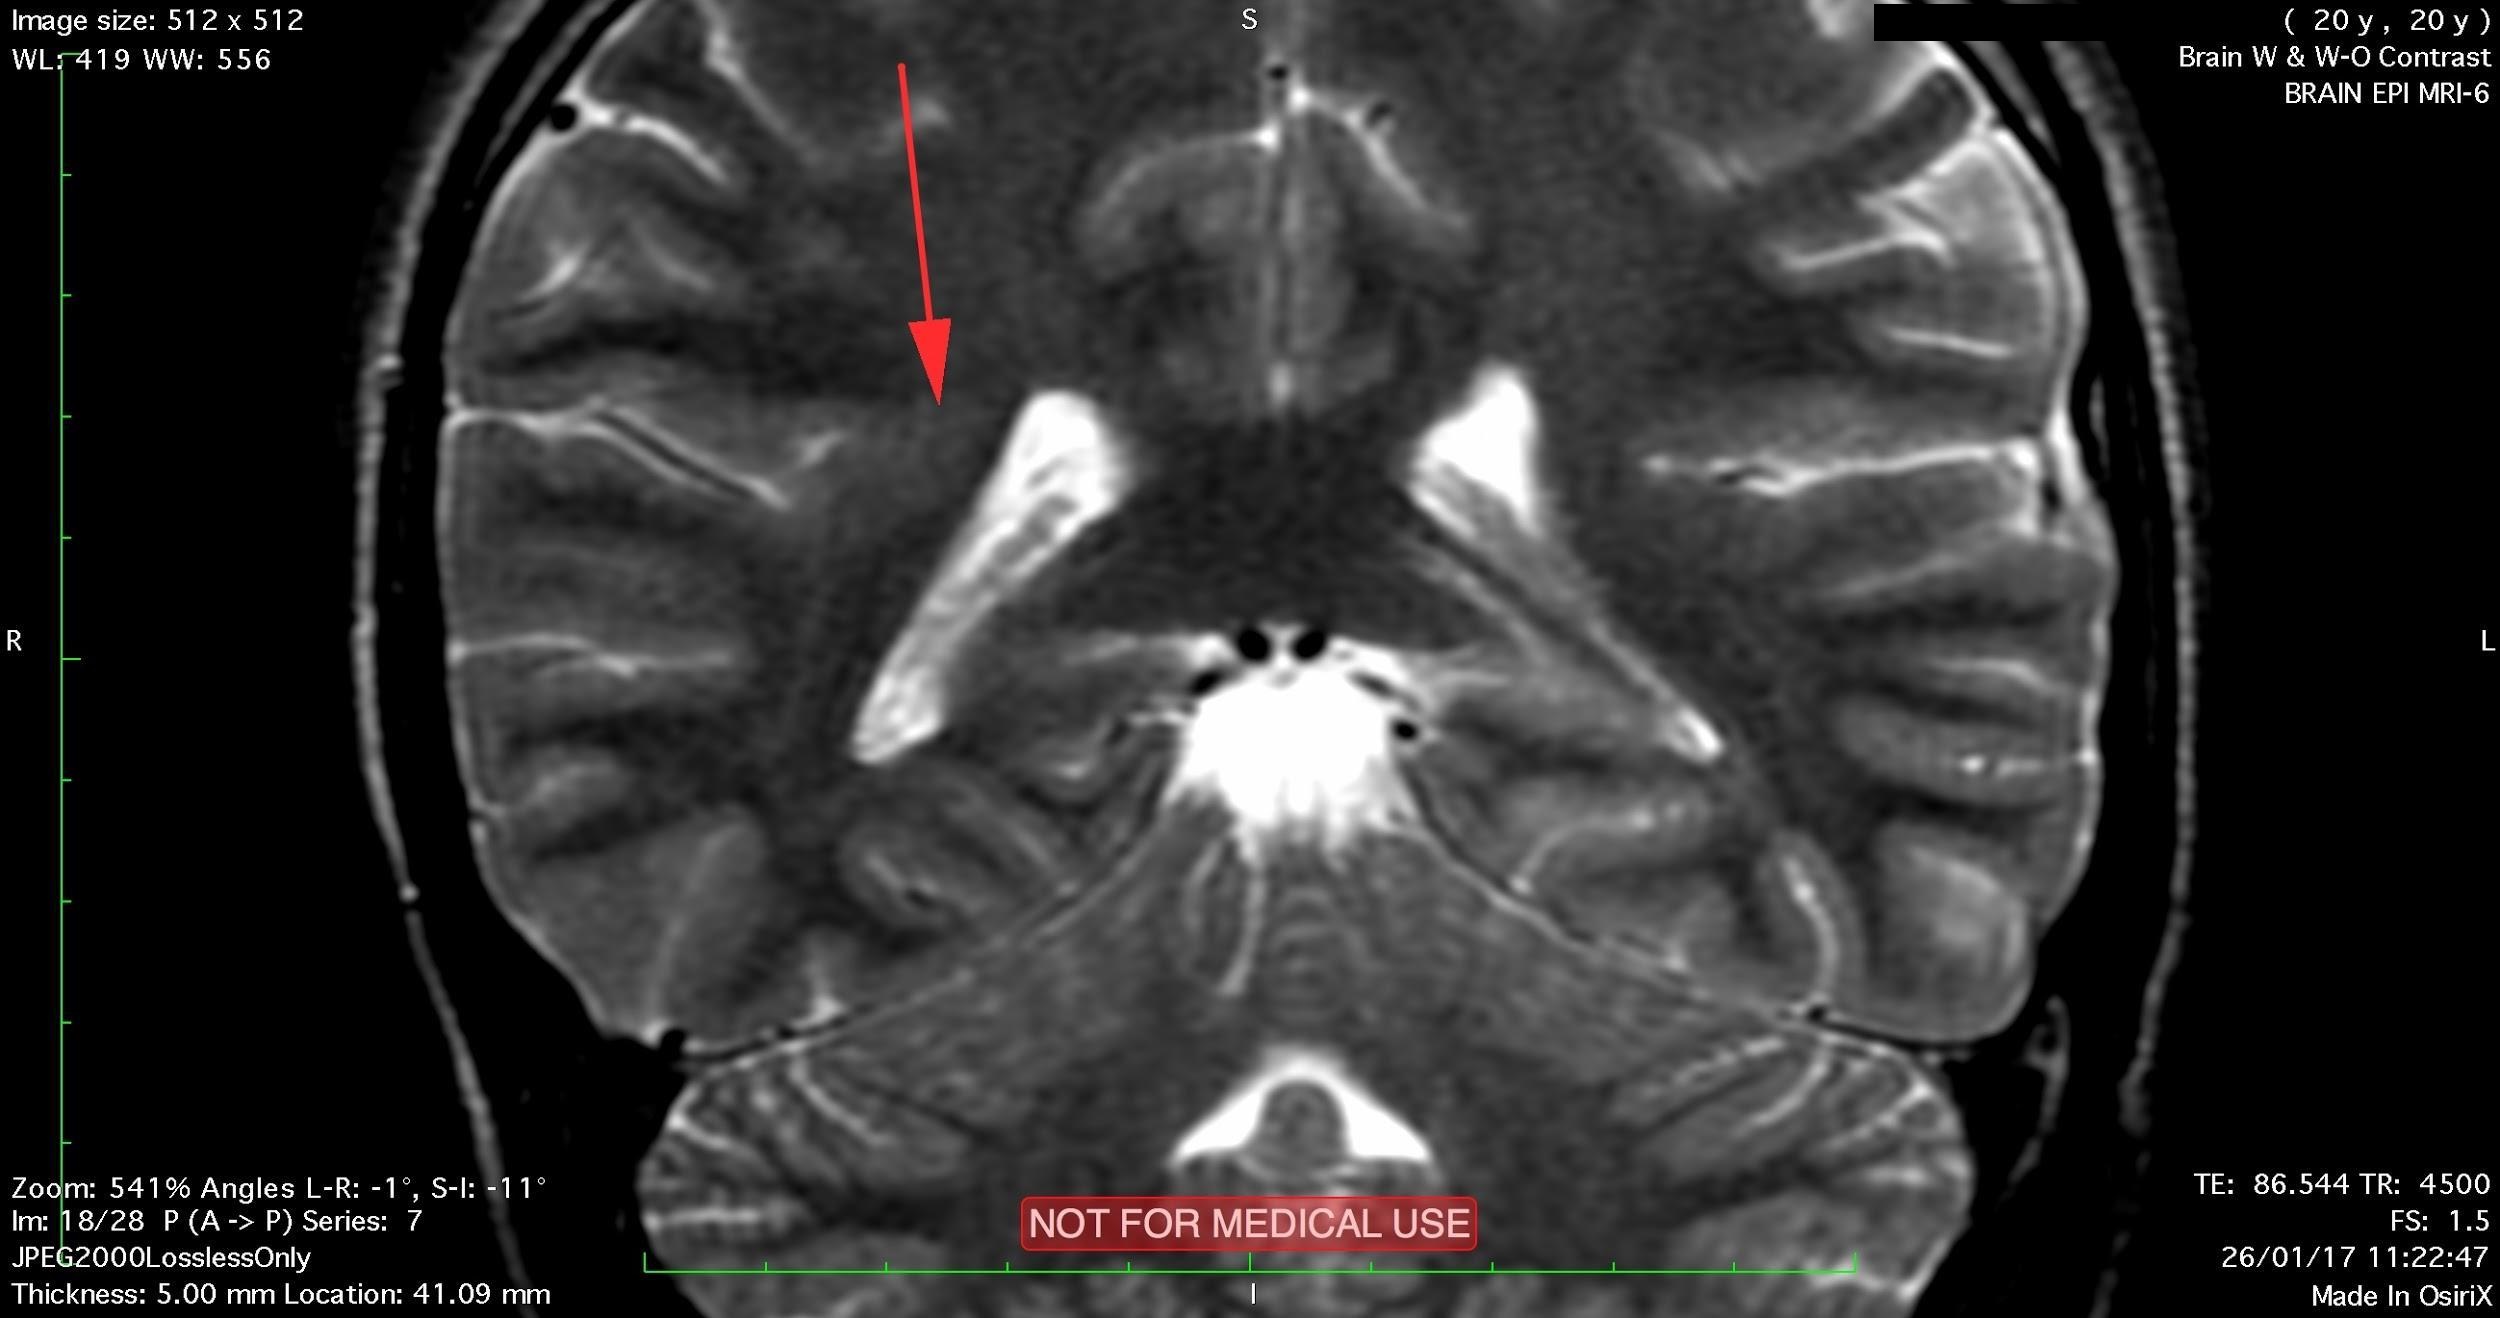

A subtle linear band intensity extending between deep posterosuperior aspect of right Sylvian fissure and posterior aspect of corpus of right lateral ventricle (isointense with gray matter on all sequences). These MRI findings strongly suggest "Type II (Taylor type) focal cortical dysplasia (transmantle cortical dysplasia)" or "transmantle gray matter heterotopia". Virtually, they may be representing two different names for the same entity.

Secondary hippocampal sclerosis is identified, bilaterally (secondary to long-term intractable epilepsy).